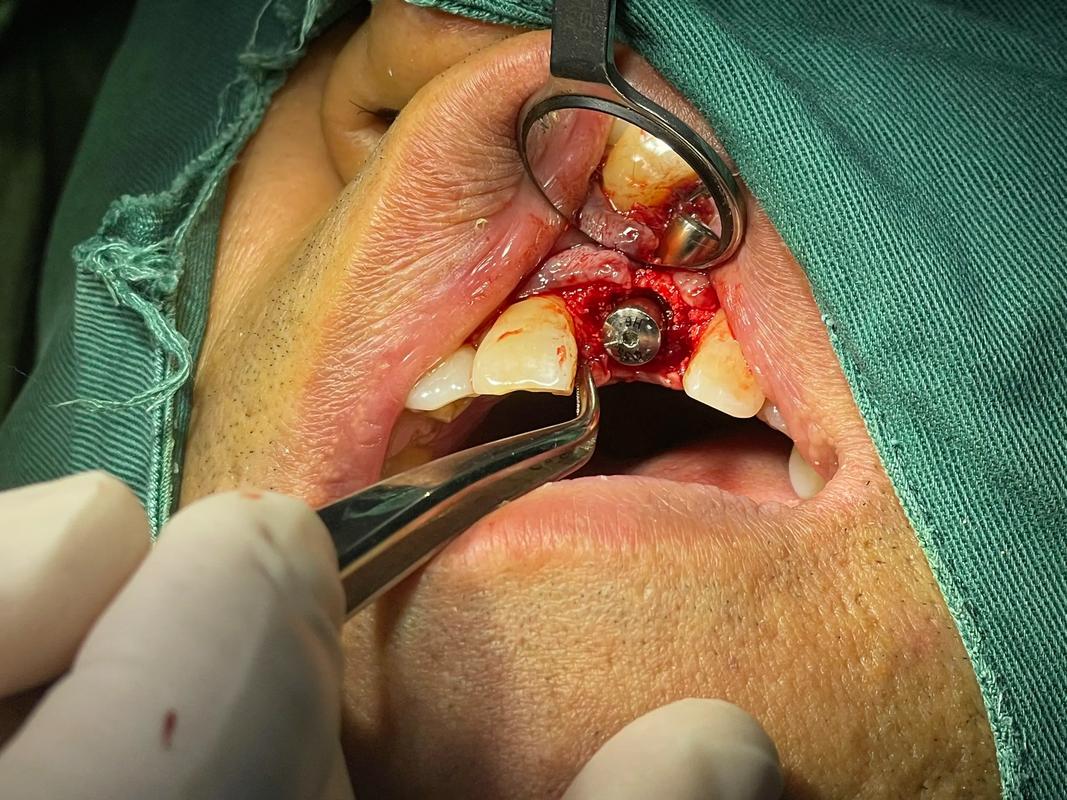

📍 针对骨量不足的解决方案(通常需要植骨)

- 引导骨再生术: 这是最常用的方法,通过在骨缺损处放置特殊的骨移植材料(自体骨、异体骨、异种骨或人工骨),再覆盖生物膜引导骨细胞生长,从而增加骨量,这通常需要3-6个月的愈合期,待新骨形成后再植入种植体。

- 植骨手术: 如前所述,根据骨缺损情况选择合适的植骨方法。这可能是第一步,也是最关键的一步。

- 种植体植入手术: 在骨量充足且稳定后,进行种植体植入手术,手术时间通常较短(单颗牙几十分钟),但术后需要3-6个月的骨结合期(种植体与牙槽骨长牢)。